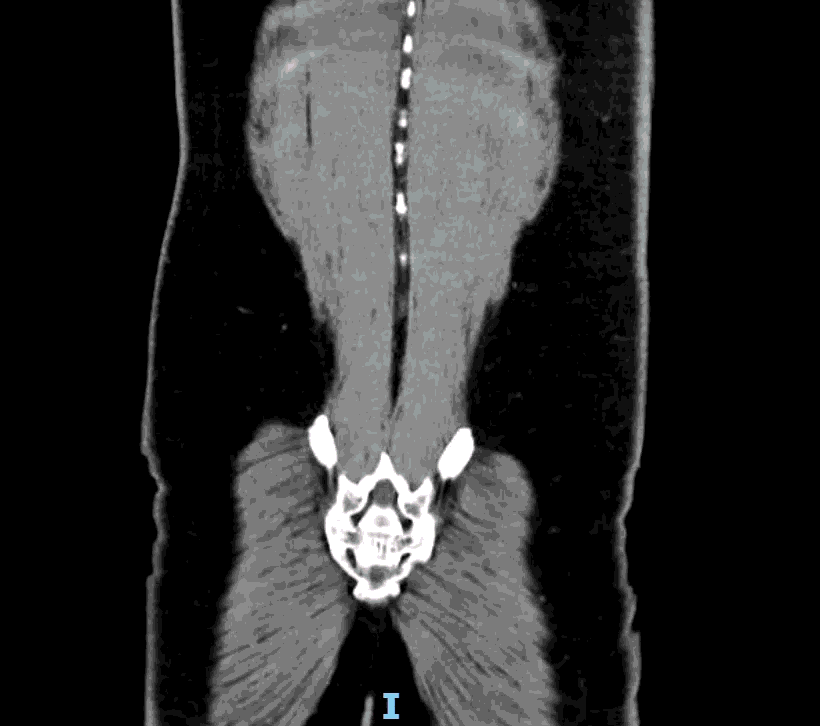

CT impression :

Right lower quadrant mid ileum 5.4 x 3.5 x 3.3 cm diverticulum, which may represent Meckel's diverticulum, containing calcifications/stones. Surrounding inflammatory fat infiltration suggesting Meckel's diverticulitis. Proximal small bowel distention with air-fluid levels, which may represent ileus versus partial small bowel obstruction. Unremarkable appearing appendix.